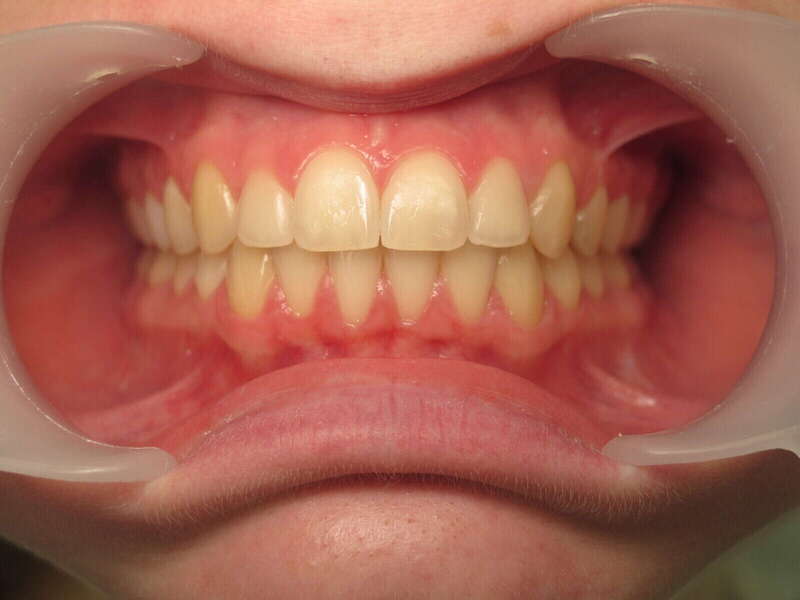

Cas n°1 traité par aligneurs - adolescent

Ce cas d’une adolescente illustre la correction d'une Classe II avec supraclusion par aligneurs. La stratégie thérapeutique a reposé sur une distalisation séquentielle de l'arcade supérieure. Ce mouvement précis a permis de reculer les dents maxillaires étape par étape pour annuler le surplomb (overjet) sans extractions.

Résultats clés :

• Correction fonctionnelle : Retour à un engrènement de Classe I stable et correction du recouvrement vertical.

• Esthétique restaurée : Harmonisation globale du sourire et du profil.

• Approche moderne : Un traitement discret, confortable et hautement prévisible.

Le résultat final montre une occlusion saine et un sourire parfaitement aligné, garantissant une santé dentaire et articulaire optimale pour l'avenir.